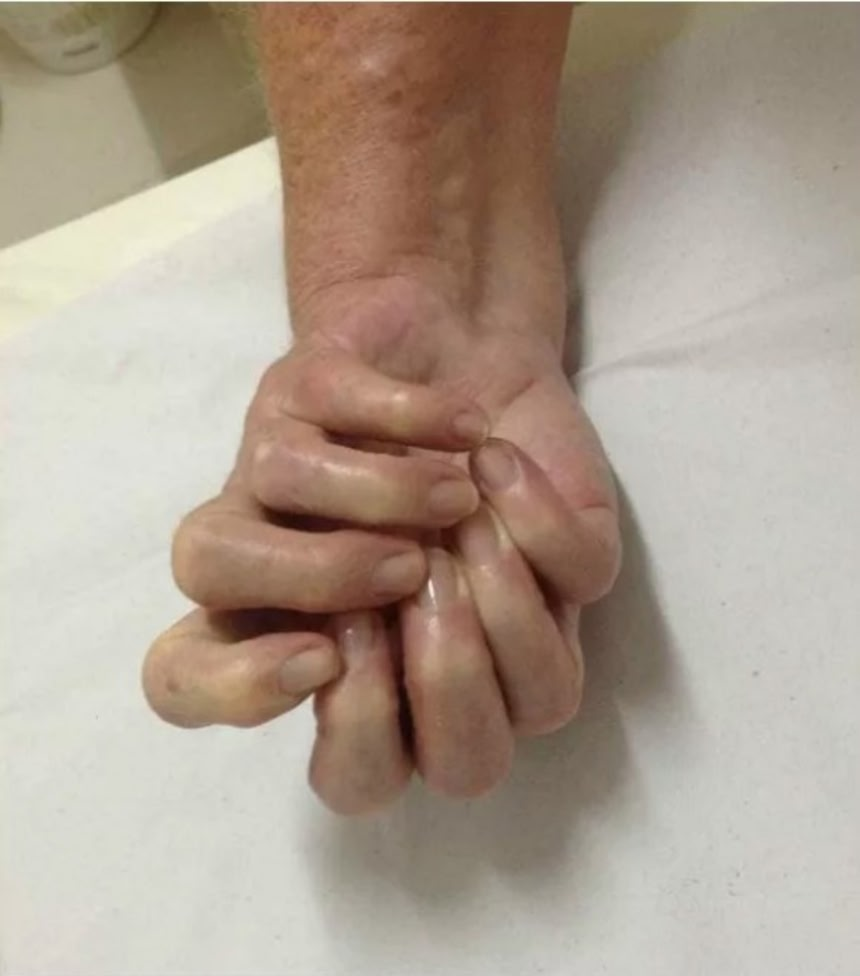

この画像を大きなサイズで見る海外のネット上をにぎわしていた8本指の手の画像がある。

それは親指の無い8つの指を持つ手の画像だ。コラ疑惑も浮上しているのだが、病名、レントゲン画像と共に公開されていた為、真偽のほどがわからない状態となっていた。

2018年4月、親指の無い8つの指を持つ手の画像が海外で拡散されていった。海外掲示板やfacebook、twitterなどでも出回っていたので、見たことある人もいるのではないだろうか?

その画像の説明によると、手足の先天性の形状異常の一種、多指症の中でも極めて珍しい「尺側重複肢症(Ulnar dimelia)」(別名:ミラーハンド)患者の手だという。

ネット上で出回って8本指の手の画像

この画像を大きなサイズで見る当初は偽物だという意見が多かったが、多指症は確かに存在する。病の本質を理解すると「実物の写真ではないか?」という声も大きくなった。